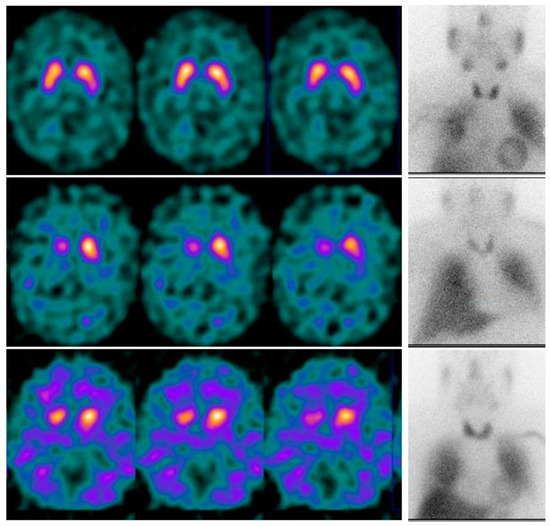

| [123I]Ioflupane SPECT | [123I]MIBG Scintigraphy | |

|---|---|---|

| Sensitivity | 95.24% (87.61–100) | 78.57% (64.97–92.17) |

| Specificity | 25% (0.00–79.93) | 50% (0.00–100) |

| PPV | 93.02% (84.25–100) | 94.29% (85.17–100) |

| PNV | 33.33% (0.00–100) | 18.18% (0.00–45.52) |

| Accuracy | 89.13% | 76.09% |